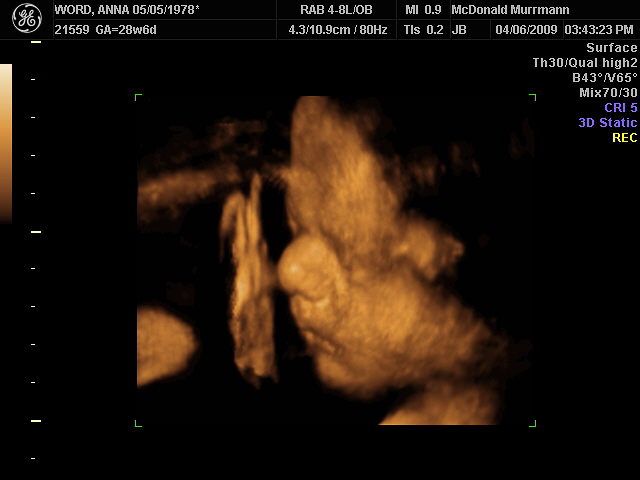

Los Ultrasonidos 4D utilizan ondas sonoras de alta frecuencia para crear imágenes tridimensionales y en tiempo real del feto. Estas imágenes permiten a los médicos ver detalles importantes, como la anatomía y el movimiento del feto, lo que les ayuda a detectar cualquier problema de salud a tiempo. Además, la tecnología 4D también permite a los padres ver a su bebé en desarrollo y tener una experiencia única y emocionante antes de su nacimiento.

La precisión de los Ultrasonidos 4D es otro aspecto importante que los convierte en una herramienta valiosa en el seguimiento del embarazo. La tecnología avanzada utilizada en los Ultrasonidos 4D permite una imagen clara y detallada del feto, lo que ayuda a los médicos a detectar cualquier problema de salud tempranamente. Además, los Ultrasonidos 4D también pueden ser utilizados para medir la cantidad de líquido amniótico, lo que es importante para evaluar el crecimiento y desarrollo del feto.